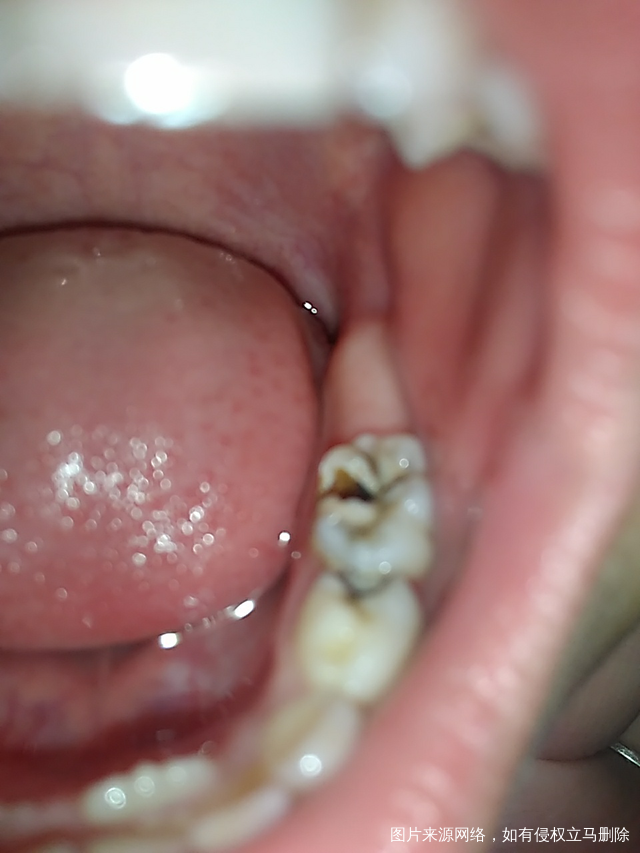

宝贝换牙了,我还一脸懵,奇怪,说这牙咋怎回事,每天都刷牙洗脸,还有蛀牙,牙科医生说孩子嘛,都有蛀牙,咋们大人也是有蛀牙,就是少吃糖就行,吃糖,孩子避免不了的,哪个孩子不吃糖呢?必须早晚勤刷牙,刷牙时间是两分钟,饭后也刷牙

宝贝那天吃鸭腿了,说骨头卡在牙缝里,我用牙签挑不出来,用针去挑,宝贝过了很久都说龋齿那疼,说牙尖上摩擦疼,后来我知道不能这样挑牙,会加重牙齿疼痛,对牙齿不好

还看见,乳牙未掉,恒牙长出来了,我说等周六去牙科,去了牙科那,牙科医生说了,必须把乳牙拔了,不然影响美观不说,还影响恒牙生长,从进去牙科医院,到躺着上麻药拔牙,拔牙完了,结合医生的那些消炎药,有琥乙红霉素颗粒,双黄连口服液,漱口水,结果我家闺女对那个漱口水过敏了,回来手上起来红点,又去诊所买了抗过敏药物,吃了好点,但是脸上还有点过敏后没有完全排出来的毒素,导致脸上一热起来湿疹,又把抗过敏药物吃了,配合999皮炎平用了才好了